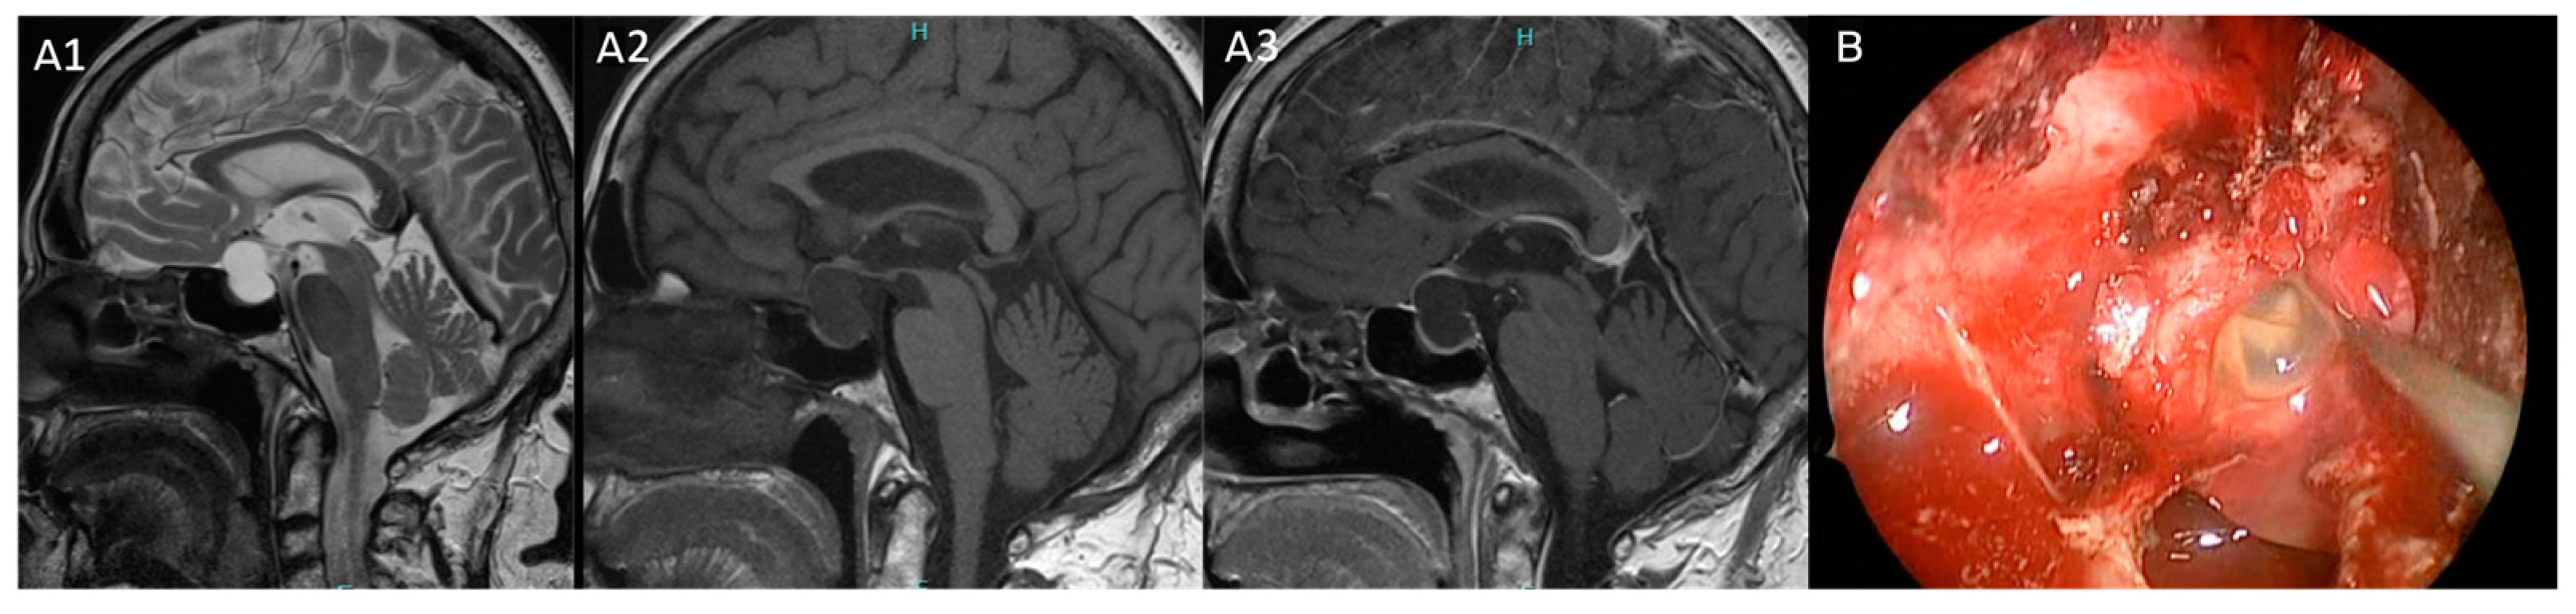

Figure 3. (A,B): Pituitary MRI and intraoperative view of patient 16. (A1) Preoperative T2-weighted of targeted pituitary MRI in coronal plane show a sellar–suprasellar cyst characterized by hyperintensity of signal in the cranial content and inhomogeneous signal in the sellar portion. (A2) Hyperintensity of signal on T1-weighted MRI sequence. (A3) No contrast enhancement on T1-weighted with Gadolinium of pituitary MRI sequence. (B) The intraoperative view shows the granular content of the cyst. This patient experienced headache, visual defects and hypopituitarism.

Our proposed model computed the several correlations found between radiological and clinical features of Rathke’s cleft cysts in our series to improve their treatment with a patient-tailored strategy. A first important aspect that emerged from our study is the strong association between RCCs and endocrine dysfunction, underlining the impact of hormonal evaluation in these patients. Specifically, hypopituitarism and headaches were observed in patients with cysts hyperintense on T1-weighted MRI sequences subsequently correlated to chronic inflammation, squamous metaplasia at histopathological investigation and correlated to intraoperative granular or mucoid elements cystic content. These findings align with previous studies [18] confirming the paramount role of inflammation and squamous metaplasia in the development of postoperative hypopituitarism. Notably, hypopituitarism did not improve with surgery, and new postoperative hormonal deficits were observed in 16% of patients in our series. Conversely, RCCs with a CSF-like content (hyperintensity on T2-weighted MRI sequences and hypointensity on T1-weighted MRI sequences) demonstrated more indolent cystic behavior and a lower incidence of inflammation on histopathological specimens [7] (Figure 3 and Figure 4).